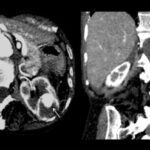

La Categoría III muestra engrosamientos lisos o irregulares de la pared o de los septos intra quísticos y existencia de realce medible en TC y RMI. Se consideran masas indeterminadas y precisan de primera instancia cirugía, nefrectomía parcial o ablación por radiofrecuencia, salvo contraindicaciones clínicas.(19, 21) Aproximadamente el 40%-60% son lesiones malignas (carcinomas renal quístico), siendo el restante benignas, que incluyen quistes hemorrágicos, infectados crónicos o calcificaciones parietales, nefrona quístico multiloculado, quistes multilobulados, quistes con tabiques complejos, etc. (Anexos 9 y 10).

La Categoría IV presenta captación de un componente sólido intra quístico, muestra realces nodulares fuera de la pared y de los septos interpuestos en el área quística compleja, calcificaciones gruesas, vascularizadas con un importante realce con contraste yodado IV. En realidad, son lesiones malignas con componente quístico. Se trata de neoplasias quísticas, y precisan cirugía y estadificación.(19, 21) (Anexos 11 y 12).